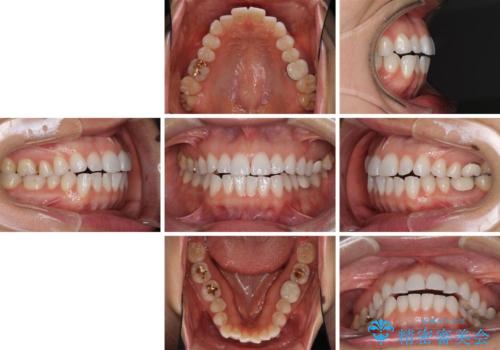

ちょっとしたデコボコをしっかりと改善したい インビザライン矯正

- 前歯のデコボコと上下スペースと前歯の隙間を気にして来院された患者様です。

目立たない装置を希望とのことでインビザラインにより、デコボコを解消しつつ、上下の前歯の隙間を閉じていくこととしました。

デコボコはあっという間に解消されましたが、上下前歯の隙間がなかなか解消されませんでした。

飲み込みの際に舌を前方に突出する癖があり、飲み込みの度に前歯に強く接触していたため、上下前歯の隙間が維持されていました。

舌の訓練を徹底していただいたことで、徐々に隙間は解消され、きれいな歯列に整えることができました。